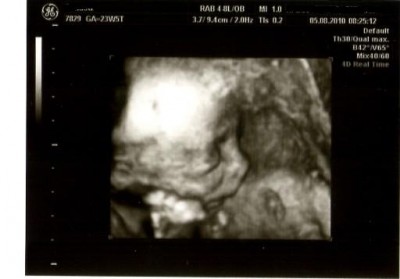

US war mal wieder super, Mia entwickelt sich völlig zeitgerecht und ist sehr aktiv. Der Doc hat auf 4 D umgestellt und dann konnten wir beobachten wie sie mit den Ärmchen hin und her wackelt und ihr Gesicht in den Mutterkuchen drückt, auch schiebt sie sich die Nabelschnur vor der Nase immer hin und her.

Mia hat eine total süße Stupsnase-oh ich bin verliebt! :P

Ich hoffe ihr könnt gleich was auf den US Bild erkennen.

@leo: Ohhhhhhhhhhhhhhhh, was für ein schönes Bild :knuddel: (*will auch endlich zum Arzt*) - und siehst du, diesmal war sie fotogener *g* Klasse, dass es dir auch sonst gut geht!!!! Weiterhin :knuddel: Freue mich riesig für dich!!!!